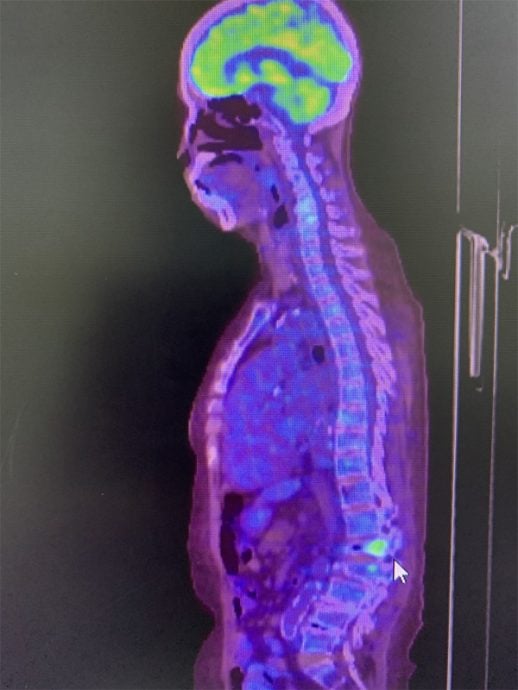

正电子发射断层扫描(PET scan)显示L1塌陷。

在肿瘤科医生的建议下,陆妈妈来到我的诊所。她年纪不算太大,但却比同龄人更佝偻龙钟,由于背痛无法久站,所以女儿用轮椅推着她进来。我细看她们带过来的正电子发射断层扫描(Positron emission tomograhy, PET scan),发现造影图上只有腰椎崩塌处亮起高代谢信号,其他身体部位并没有亮信号,以我的经验来看,我推测陆妈妈很大可能纯粹是骨质疏松,造成腰椎崩塌,而不是癌症导致病理性骨折。